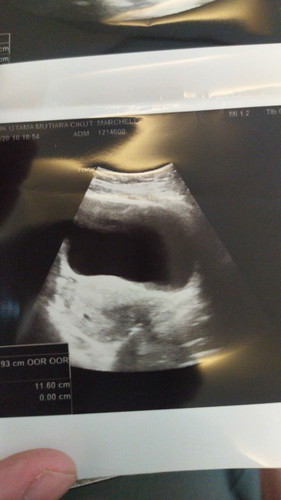

Bun.. kalo hamil sekitar 5 to 6 weeks kalo usg memang cuma setitik gitu ya?

usg perut bun

Ya memang seperti itu bun terlihat kantong nya saja